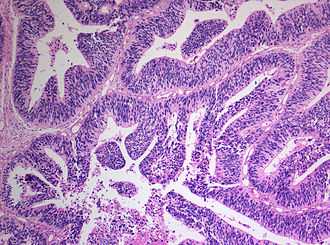

При поступлении на заднебоковой поверхности шеи слева у больного определялось умеренно болезненное, плохо смещаемое относительно окружающих тканей узловое образование плотной консистенции размером 10—15 см; кожа над ним гиперемирована. Выполнена трепанобиопсия. По результатам гистологического и иммуногистохимического исследования установлен морфологический диагноз — PNET (рис. 1, на цв. вклейке). Рисунок 1. Примитивная нейроэктодермальная опухоль. а — иммуногистохимическая реакция с антителами к CD 99. ×400. Рисунок 1. Примитивная нейроэктодермальная опухоль. б — окраска гематоксилином и эозином. ×400. Клинический диагноз: нейроэктодермальная опухоль (PNET) заднебоковой поверхности шеи слева T2NХM1 (метастазы в легких и плевре).